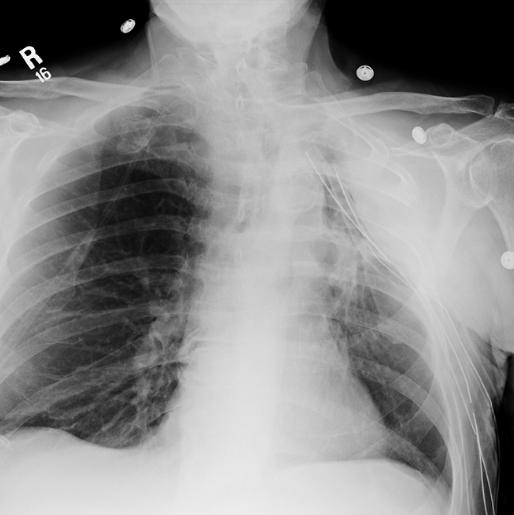

This 52 year old man had recent left thoracic surgery for a Pancoast tumor and had three chest tubes placed in the OR. What kind of radiograph do you think this is and what do you think of the position of the chest tubes?